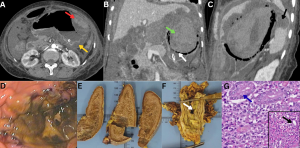

Fig 21: Case 1 -

A middle-aged male with uncontrolled diabetes mellitus and recent corticosteroid exposure, a diagnosed case of disseminated mucormycosis, presented with fever and sepsis.

Figures A & B:

Figure A: Magnified ultrasound image demonstrates multiple hypoechoic lesions in the liver (red arrows).

Figure B: Axial contrast-enhanced CT (CECT) abdomen image demonstrates multiple hypodense, hypoenhancing lesions in the liver (green arrows), consistent with hepatic microabscesses.

......Case 2 -

Clinical history:

A diabetic male with recent COVID-19 infection and corticosteroid exposure, a diagnosed case of disseminated mucormycosis, presented with persistent fever and abdominal pain.

Figures C & D:

Figure C: Magnified ultrasound image demonstrates multiple hypoechoic lesions in the spleen (orange arrows).

Figure D: Axial contrast-enhanced CT (CECT) abdomen image demonstrates multiple hypodense, hypoenhancing lesions in the spleen (yellow arrows), consistent with splenic microabscesses.